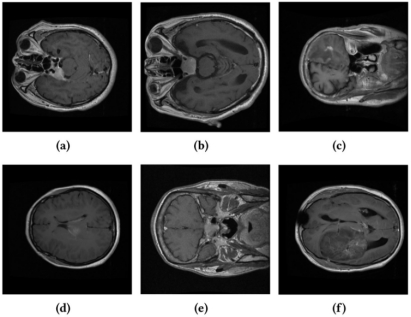

圖1 醫(yī)學(xué)圖像中的類間相似性與類內(nèi)差異性示例。張瀟供圖

在醫(yī)療領(lǐng)域,對(duì)海量高維醫(yī)學(xué)影像數(shù)據(jù)進(jìn)行高效管理和可靠分析是一項(xiàng)關(guān)鍵且嚴(yán)峻的挑戰(zhàn),尤其是在資源有限的情況下,如遠(yuǎn)程醫(yī)療設(shè)施和移動(dòng)設(shè)備中,這一需求更為迫切。為了應(yīng)對(duì)這一挑戰(zhàn),有效的數(shù)據(jù)集壓縮技術(shù)顯得尤為重要,它可以降低存儲(chǔ)、傳輸和計(jì)算成本。然而,現(xiàn)有的核心集選擇(Coreset Selection)方法主要針對(duì)自然圖像數(shù)據(jù)集設(shè)計(jì),尚未充分考慮醫(yī)學(xué)圖像領(lǐng)域的特定需求。醫(yī)學(xué)圖像數(shù)據(jù)集具有類內(nèi)差異性(intra-class variation)和類間相似性(inter-class similarity)等特性,導(dǎo)致現(xiàn)有方法在醫(yī)學(xué)圖像上的表現(xiàn)不佳。